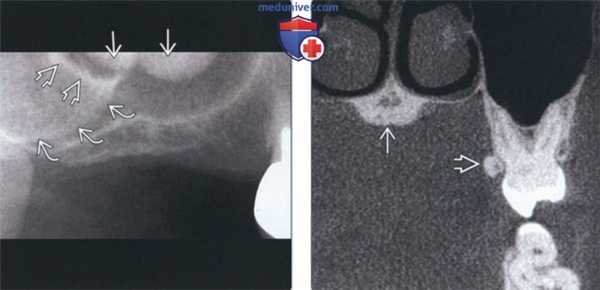

(Слева) На периапикальной рентгенограмме правой половины верхней челюсти у пациента с отсутствующими зубами определяются хорошо отграниченные рентгеноконтрастные наложения в верхних отделах верхнечелюстной пазухи, представляющие собой небный валик с фестончатыми краями. Визуализируется серповидное затенение (скуловой отросток верхней челюсти) и распространяющийся кзади рентгеноконтрасгный участок (нижний край скуловой кости).

(Справа) На корональной КЛКТ визуализируется маленький небный валик в средних отделах неба. Обратите внимание на небный экзостоз. Экзостозы часто сочетаются с небными валиками.